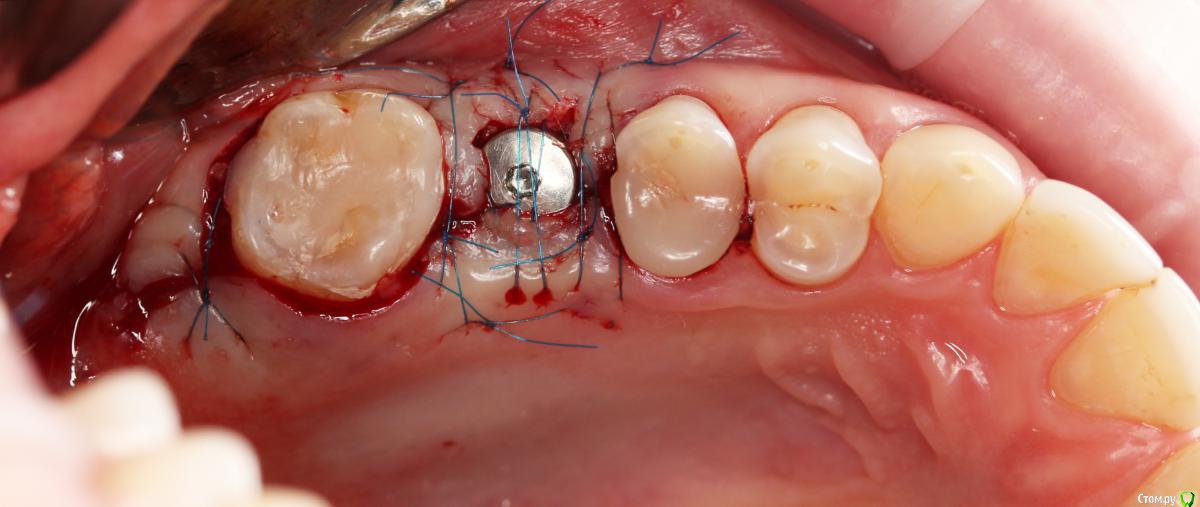

Dmitry DK Опубликовано 10 сентября, 2019 Поделиться Опубликовано 10 сентября, 2019 Фотопротокол к сожалению не полный, но ничего особенного и не проводилось. 1) Открытый синус, удален пломбировочный материал из пазухи, уложен 1 г Bio-oss 2) через 6 мес имплантация Straumann SP 4.1\10 Результат через год 9 Ссылка на комментарий